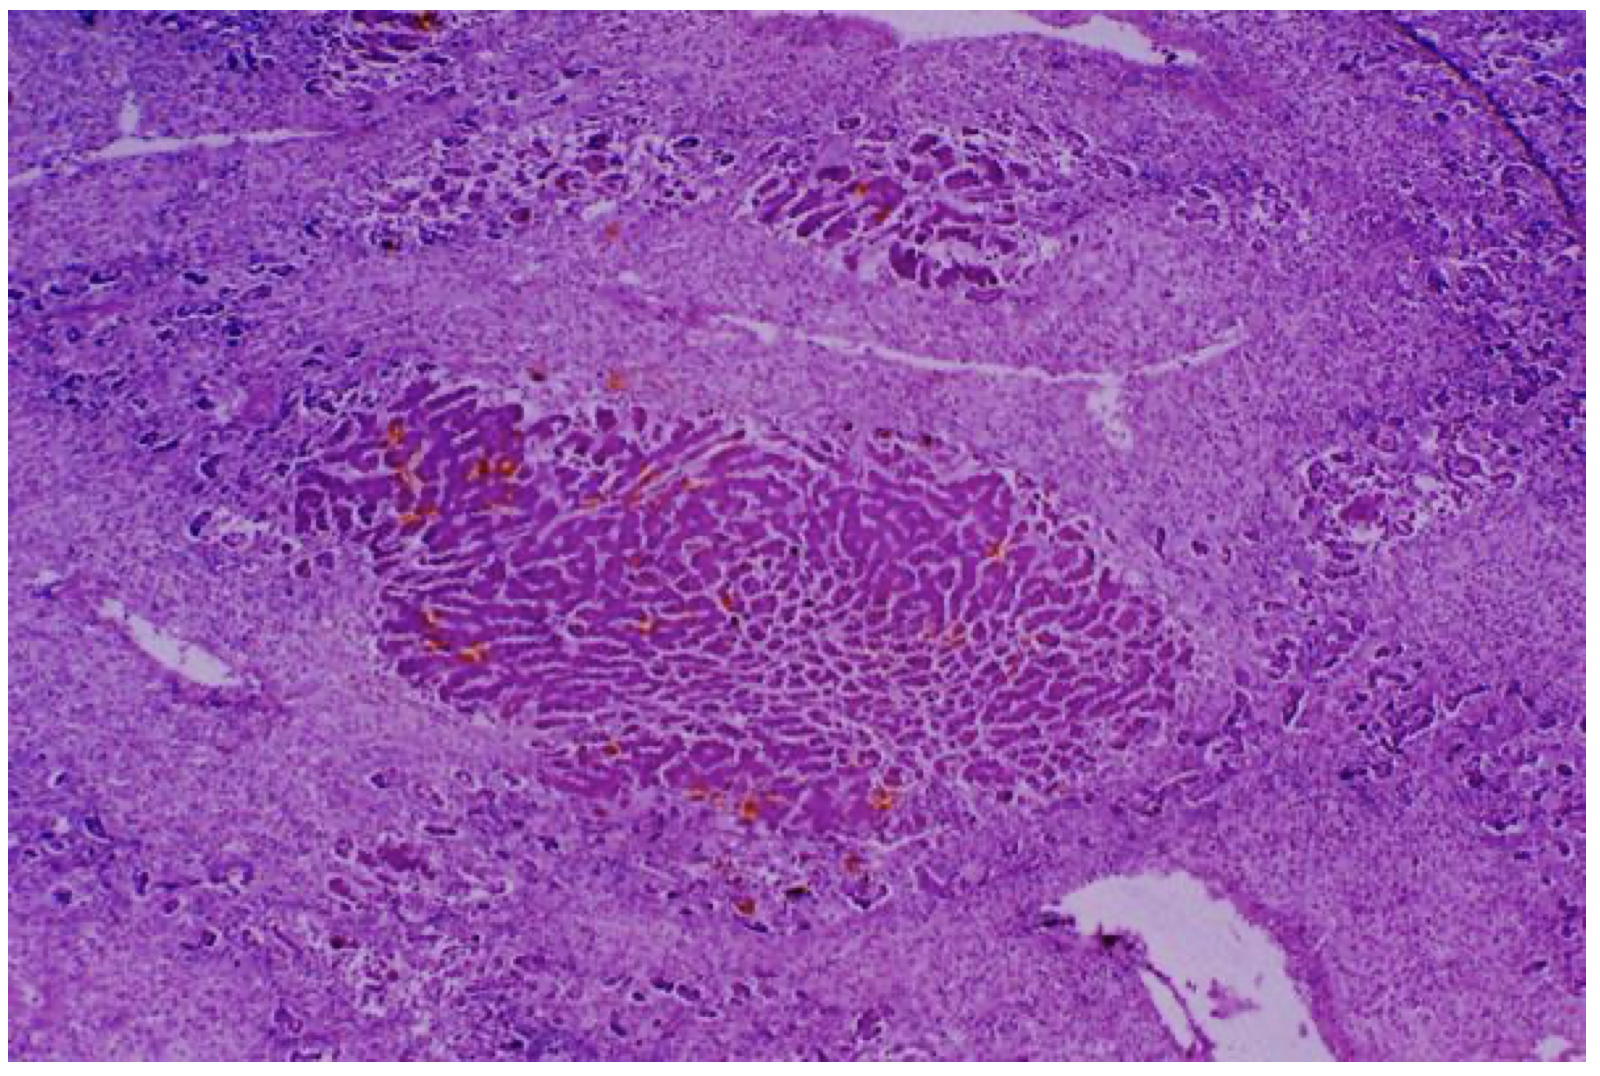

Granulation tissue, base of duodenal ulcer, H/E x 100

This photomicrograph shows the essence of granulation tissue: young, plump fibroblasts; collagen; chronic inflammatory cells; and angiogenesis, typified by young capillaries with swollen endothelial cells. If the chronic irritation is erradicated by treatment of the ulcer, the granulation tissue will slowly organize to form a mature scar, and the intestinal epithelium will regenerate over the top of it.